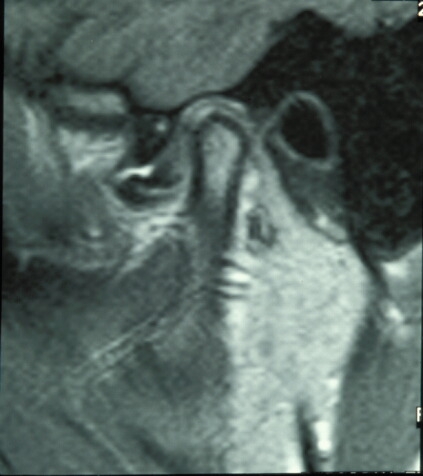

Untreated, clicking may, but not always, progress to locking, in which the disk becomes so abnormally shaped and displaced that it effectively acts like a door-stop, preventing the mandibular condyle from undertaking a full range of movements. This results in ‘locking’ of the jaw which may occur on either opening or closing of the mouth (open lock, closed lock; see Figure 2).

Normally when the mouth opens and closes the meniscus moves in harmony with the condyle as it translates along the articular eminence. In certain circumstances, however, this gliding movement is disrupted and the disk may become adherent to the fossa either by fibrous adhesions or by the so-called ‘suction cup effect’. The disk may also change shape. As a result the mandibular condyle is unable to move smoothly and may have to ‘jump’ over the periphery of the disk in order to continue moving. This movement is felt as a click.